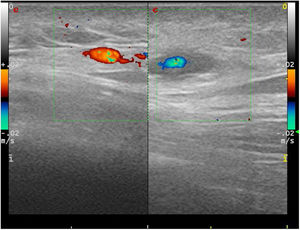

Complementary tests were performed showing a normal haemogram, with a first-hour erythrocyte sedimentation rate of 8 mm (normal 0–25), C-reactive protein 4.4 mg/L (0–10), coagulation tests with no abnormalities and complete biochemistry with nutritional profile, liver tests, renal function, thyroid function, ions, ferrokinetic profile, vitamin B12, vitamin D and folic acid within normal limits. The proteinogram, quantification of immunoglobulins including IgE, antinuclear antibodies and neutrophil antibody, rheumatoid factor and complement were negative or normal. Syphilis, HIV and hepatotropic virus serologies were negative. Chest X-ray, ophthalmological examination and urinary sediment were performed without findings. An ultrasound scan of the nodular zone was performed, and a halo in the shape of a hypoechogenic perivascular cuff and with arterial flow was obtained, suggesting a branch of the temporal artery (Fig. 1).